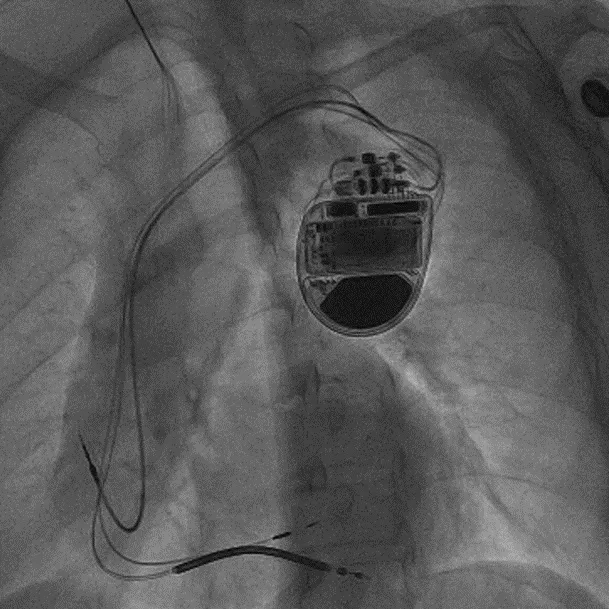

拔除无导线起搏器后植入左束支CRTD的术后影像

术前,汤宝鹏教授带领治疗团队对文献进行了详细查阅,对病情进行了充分而细致地评估,对术中可能出现的各种风险做好了各项应急预案。术中,手术团队使用圈套器成功抓捕无导线起搏器Micra尾端并顺利拔除,同时给患者植入左束支心脏再同步起搏除颤器。手术顺利,患者术后恢复良好。

该疗法实现了最大程度生理性起搏纠正心力衰竭及预防猝死的双重治疗目的,手术的顺利开展也标志着新医大一附院起搏电生理学科在该技术领域处于国际领先地位。